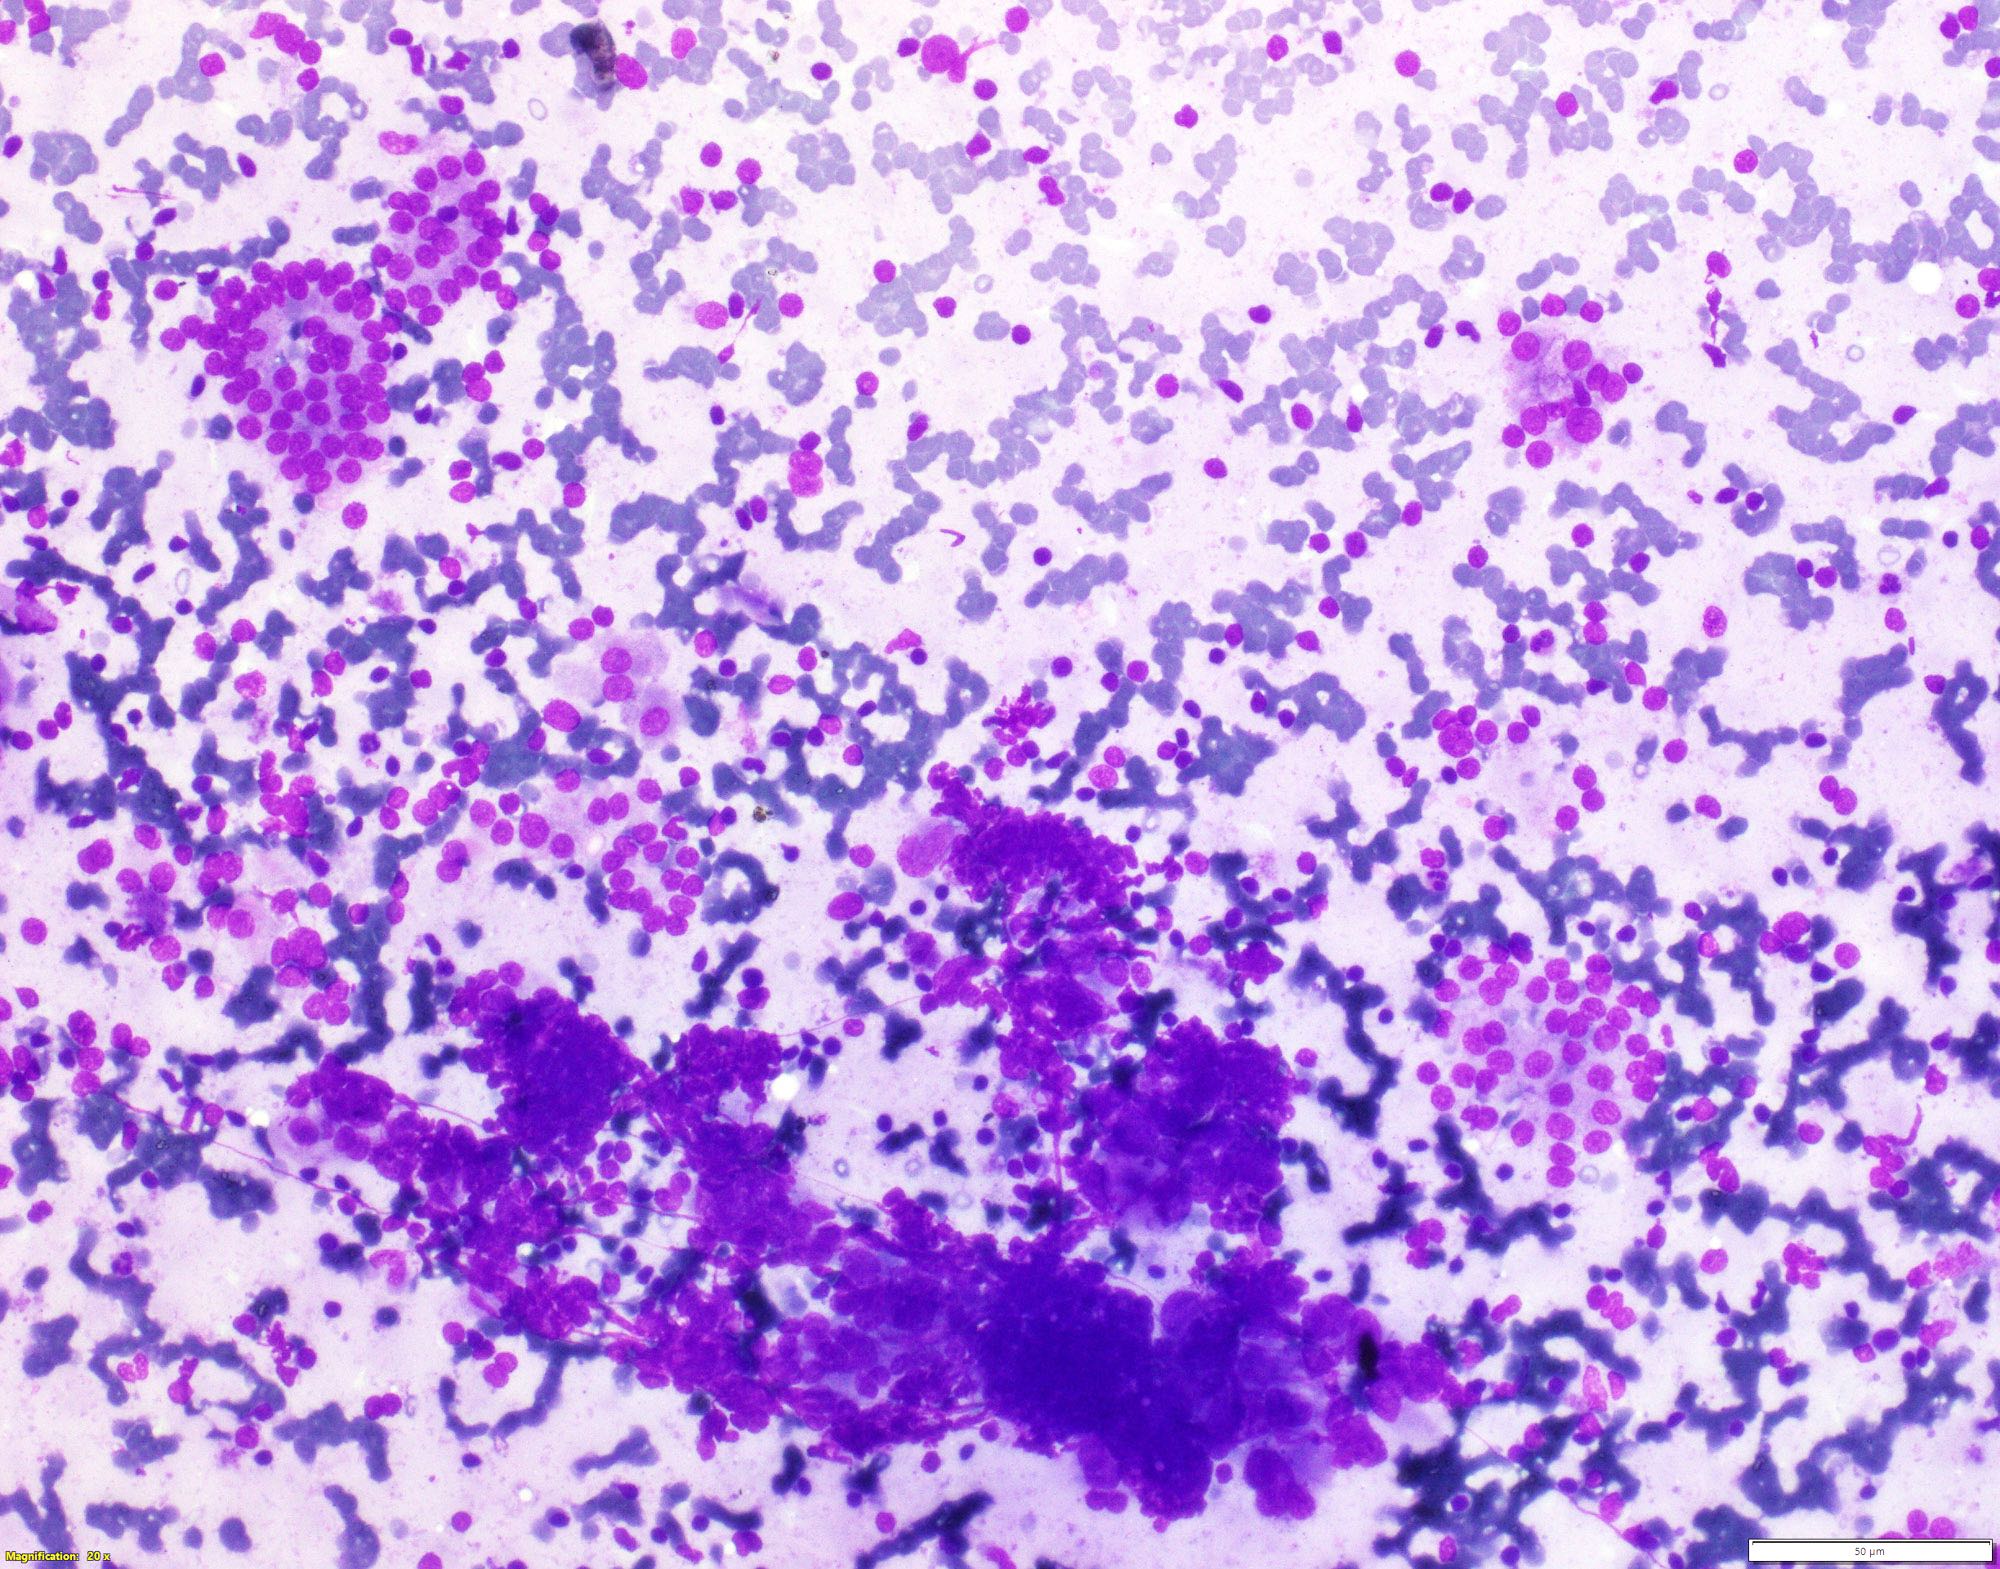

Cytology description

- Moderately or highly cellular aspirate

- Inflammatory infiltrate

- Variable number of lymphocytes in different stages of development (Cureus 2019;11:e5851, J Thyroid Res 2018;2018:5246516)

- Lymphocytes infiltrating follicular epithelial cells

- Lymphoglandular bodies (Acta Cytol 2009;53:507)

- Plasma cells

- Can grade based on lymphocytic infiltration from 0 to 3+ (see Diagrams / tables) but does not correlate with clinical, biochemical, radionuclide and ultrasonographic parameters (Cytojournal 2007;4:10, J Cytol 2016;33:145)

- Aggregates of oncocytic cells / oncocytes

- Crushed cells, lymphoid tangles

- Absent or scant colloid

- Mild anisonucleosis, giant cells, macrophages, epithelioid cells, eosinophils, fire flares

- Usually Bethesda System for Reporting Thyroid Cytopathology (TBSRTC) category II; can be TBSRTC III / IV / V

Cytology images

Contributed by Shipra Agarwal, M.D. and Ayana Suzuki, C.T.